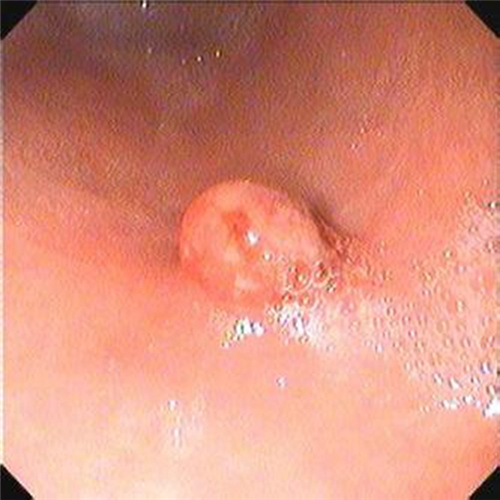

直腸息肉圖片

女性直腸息肉